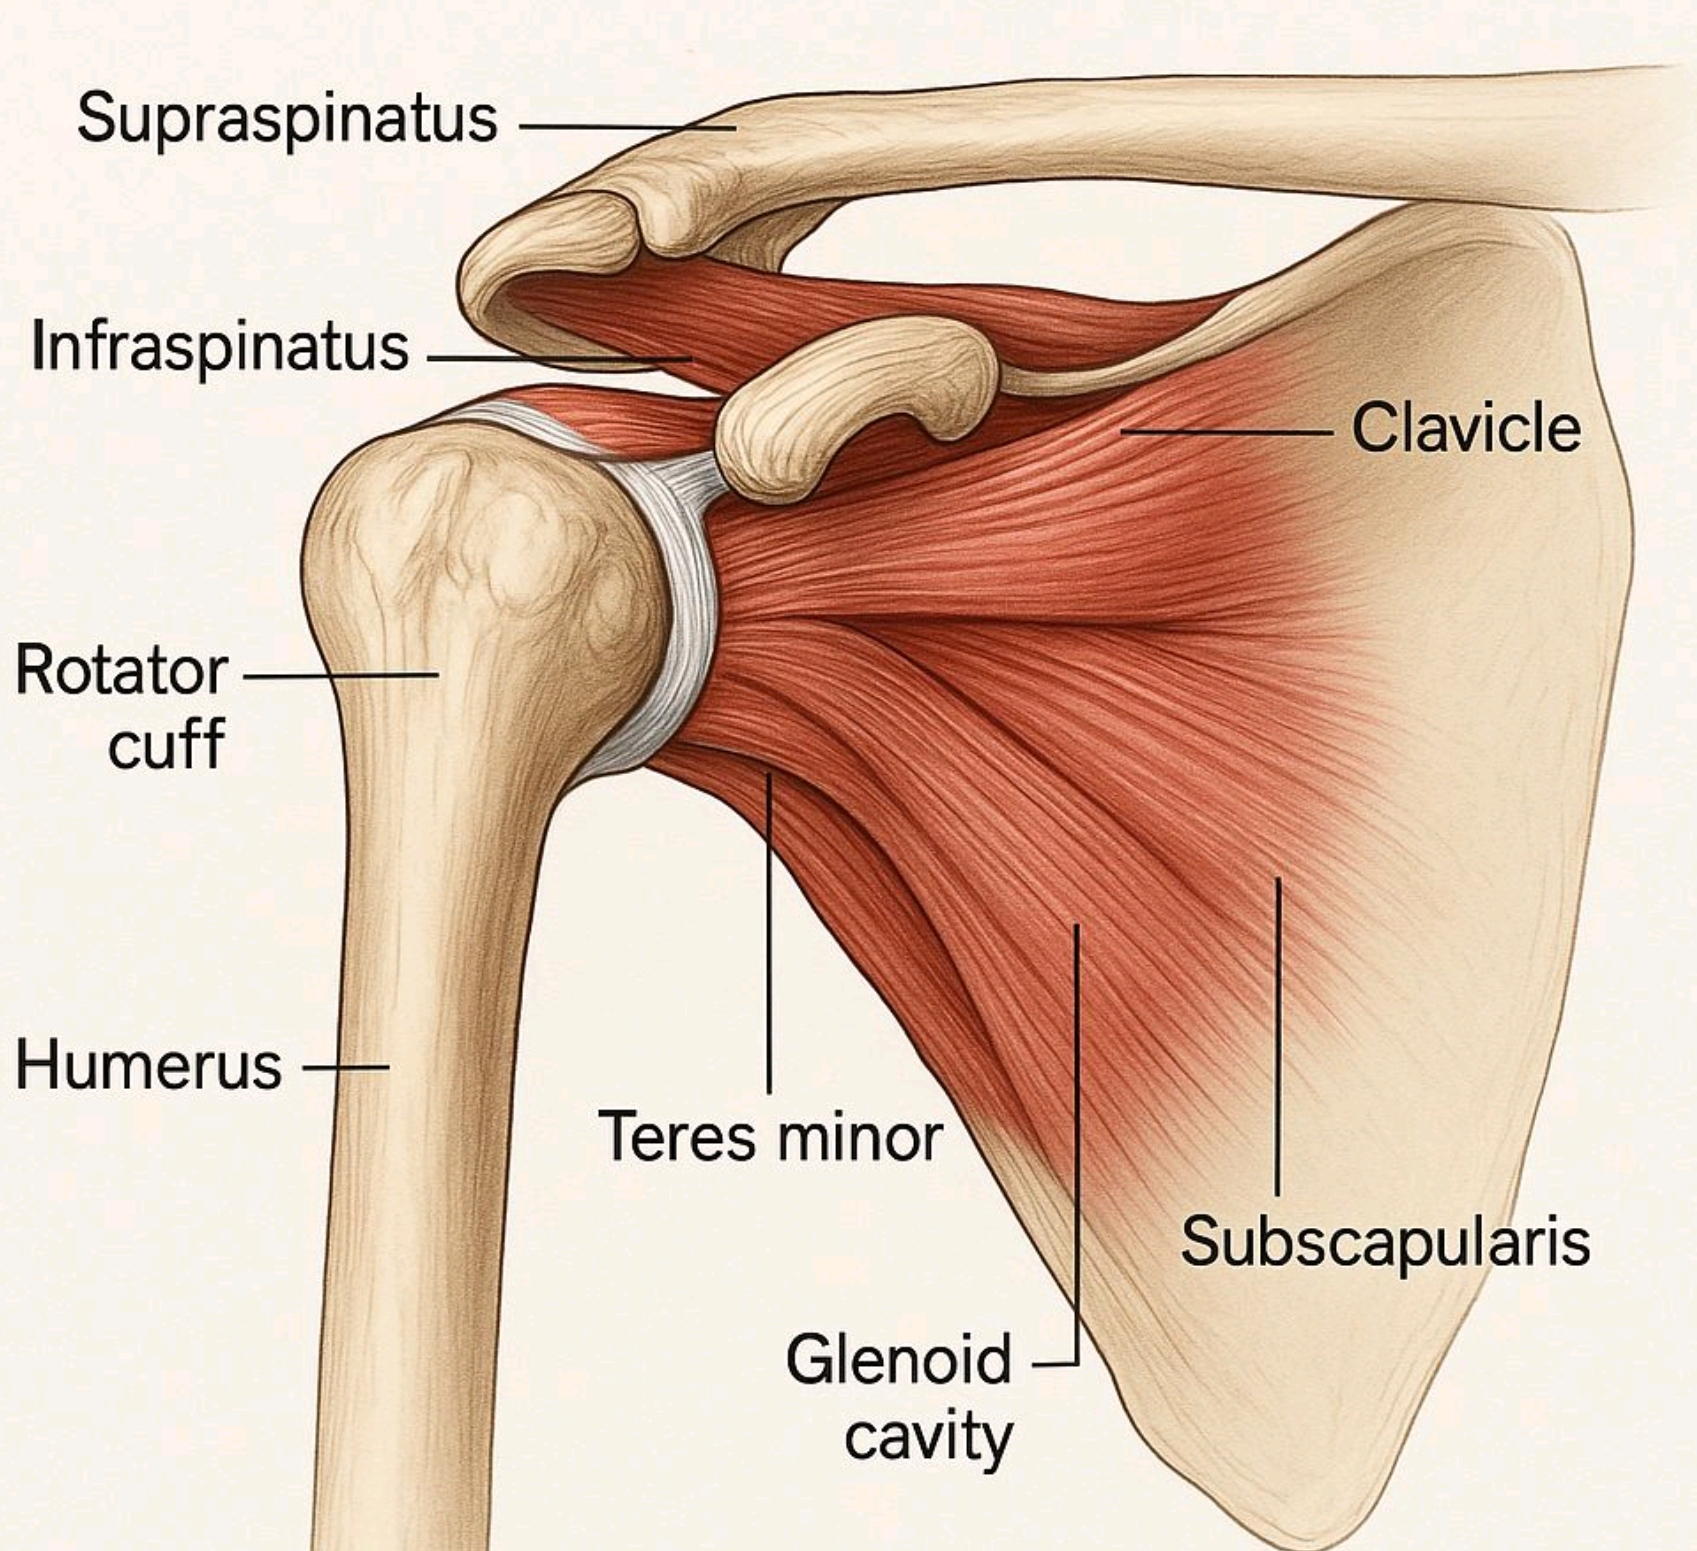

Ο ώμος είναι η πιο κινούμενη άρθρωση στο ανθρώπινο σώμα. Μια ομάδα τεσσάρων μυών και οι τένοντες τους, που ονομάζονται στροφικό πέταλο, δίνουν στον ώμο το ευρύ φάσμα της κίνησής του.

Τι είναι η Τενοντίτιδα του ώμου

Η τενοντίτιδα του ώμου προκαλείται συχνά από υπερβολική χρήση ή τραυματισμό του ώμου. Είναι συχνή σε αθλητές και σε όσους έχουν υποστεί τραύματα στον ώμο. Τενοντίτιδα του ώμου είναι η φλεγμονή των τενόντων στο στροφικό πέταλο του ώμου. Οι τένοντες αυτοί βοηθούν να σηκώσουμε και να περιστρέψουμε το χέρι μας. Επί ανάπτυξης τενοντίτιδας, οι καθημερινές δραστηριότητες γίνονται επώδυνες και δύσκολες. Ο ώμος εμφανίζει έντονη ευαισθησία, πρήξιμο και αδυναμία. Οι τένοντες που αποτελούν το στροφικό πέταλο του ώμου είναι ο υπερακάνθιος, ο υπακάνθιος, ο υποπλάτιος και ο έλασσον στρογγύλος. Οι περισσότερες τενοντίτιδες αντιμετωπίζονται επιτυχώς συντηρητικά, με περιορισμό της δραστηριότητας, αντιφλεγμονώδη φάρμακα, εγχύσεις τοπικών αναισθητικών και στεροειδών, φυσικοθεραπεία και ασκήσεις ενδυνάμωσης.

Τι είναι οι ρήξεις του στροφικού πετάλου

Το πέταλο των στροφέων του ώμου (Rotator cuff) καλύπτει στην κεφαλή του βραχιονίου και αποτελείται από τους τένοντες τεσσάρων μυών που είναι υπεύθυνοι για την έσω, έξω στροφή και απαγωγή–ανύψωση του ώμου. Οι μύες αυτοί είναι ο υπερακάνθιος ο υπακάνθιος, ο υποπλάτιος και ο έλάσσον στρογγύλος. Το στροφικό πέταλο σταθεροποιεί τον ώμο, διατηρώντας την κεφαλή του βραχιονίου οστού μέσα στην ωμογλήνη της ωμοπλάτης. Οι ρήξεις του στροφικού πετάλου διακρίνονται σε οξείες που οφείλονται συνήθως σε τραυματισμό του ώμου, και χρόνιες που είναι συνήθως εκφυλιστικής αρχής. Οι χρόνιες ρήξεις απαντώνται συχνότερα σε ασθενείς μεγαλύτερης ηλικίας και αφορούν συνήθως στον υπερακάνθιο τένοντα. Οι οξείες ρήξεις συναντώνται σε νεότερους ασθενείς, με συχνότερη την ρήξη του υποπλάτιου τένοντα. Τα συμπτώματα της ρήξης είναι αρκετά έντονα και επηρεάζουν σε μεγάλο βαθμό την καθημερινότητα του ασθενούς. Το κύριο σύμπτωμα είναι ο πόνος που εντοπίζεται στην περιοχή του ώμου, αλλά συχνά αντανακλά έως και τον αγκώνα ή/και σε όλο το άνω άκρο. Ο πόνος είναι εντονότερος το βράδυ. Συνυπάρχει η αίσθηση τριξίματος κατά τις κινήσεις του ώμου. Η κινητικότητα είναι περιορισμένη ακόμη και κατά τη διενέργεια απλών κινήσεων με ανύψωση και στροφή του άνω άκρου. Ο πόνος γίνεται πιο έντονος το βράδυ, διαταράσσοντας τον ύπνο του ασθενούς. Η θεραπευτική προσέγγιση της ρήξης έχει να κάνει με το μέγεθος της βλάβης. Η μερικού πάχους ρήξεις μπορούν να αντιμετωπισθούν συντηρητικά με περιορισμό της δραστηριότητας, φαρμακευτική αγωγή, τοπικές εγχύσεις στον υπακρωμιακό ορογόνο θύλακο και φυσικοθεραπεία σε δεύτερο χρόνο.